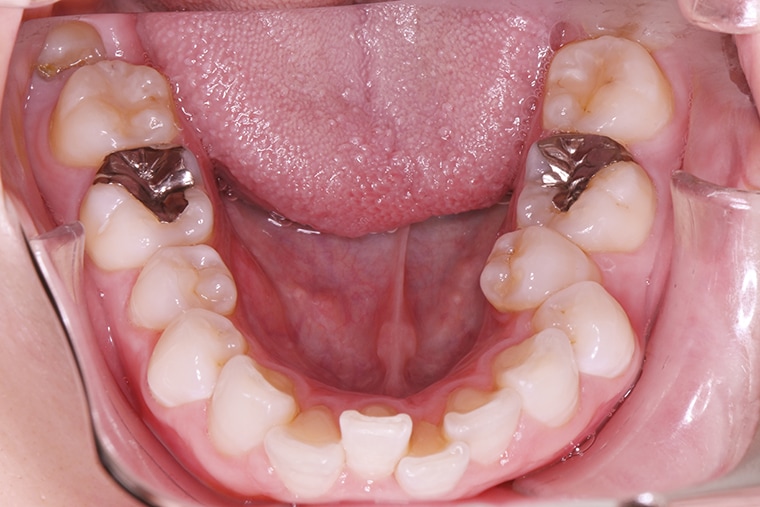

BEFORE

下の歯のガタガタがずっと気になっていたので、思い切ってマウスピース矯正を始めました。

約6ヶ月の治療を経て、下の歯のガタガタはきれいに整い、歯並びが改善されました。鏡で歯並びを見るたびに、自分の笑顔に自信が持てるようになり、以前のように口元を気にすることもなくなりました。